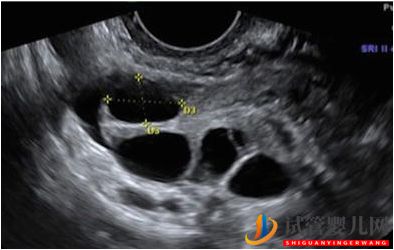

這是一個典型的超聲檢查,顯示一個卵巢有4個卵泡(中間的黑眼圈),每個都含有一個卵子。

卵泡大小和卵子質量

更大的卵泡可能是告訴人們,細胞質成熟已經發生了!

與較小的(<10毫米)相比,較大的卵泡(>18毫米)的卵子(Rosen等人,2008)。

更有可能是成熟的,有一個極地的身體更高的受精率更有可能產生高質量的胚胎

換句話說,來自更大的卵泡的卵子質量更好 !

當卵泡變得太大(>23毫米)時,這可能會導致后成熟的卵細胞。這些胚胎會顯示出質量下降(羅森等人,2008年),并且更有可能在ICSI后退化或不能受精(個人觀察)。